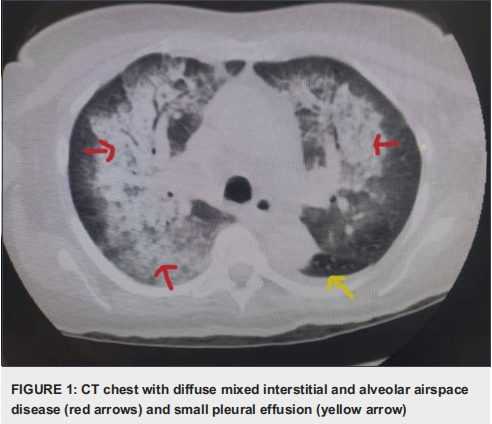

患者肾功能继续恶化,肌酐升至4.4mg/L。抗核抗体阳性,效价1:320,低补体血症(C3为53mg/dl,C4为3mg/dl)。在这一点上,鉴别诊断包括炎症后肾小球肾炎、迟发性系统性狼疮肾炎和药物性狼疮。暂停水杨酸治疗。其他相关实验室检测抗组蛋白抗体阳性9.6个单位(ref<0.1),心磷脂IgM>150(正常<20),髓过氧化物酶抗体阳性,肌酐升高至6.6mg/L,抗DNA、肾小球基底抗体和抗磷脂抗体阴性。乙肝、丙肝、HIV均为阴性。怀疑为抗中性粒细胞胞浆自身抗体(ANCA)相关血管炎,患者开始使用脉冲剂量的甲基强的松,进行肾活检用来鉴别狼疮性肾炎/免疫性肾小球肾炎。患者随后出现缺氧,临床病程恶化,被转移到重症监护室。此时胸部CT显示弥漫性混合性间质和肺泡腔疾病以及小胸腔积液(图1)。血红蛋白严重下降,需要红细胞输血。COVID-19检测呈阴性。